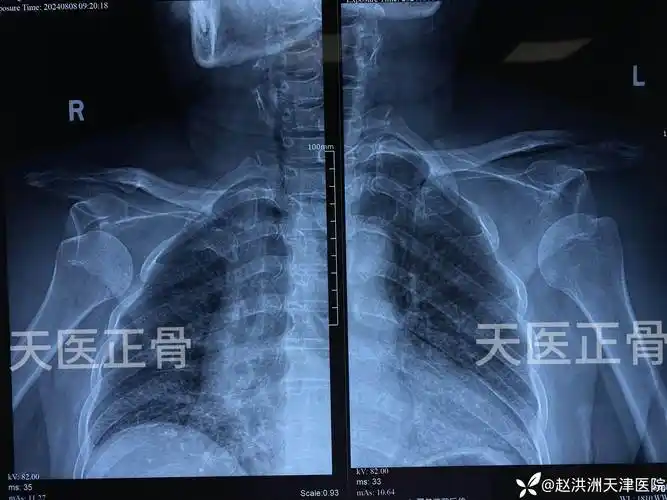

肩关节脱位那些事儿(七)—少见的双侧肩关节脱位